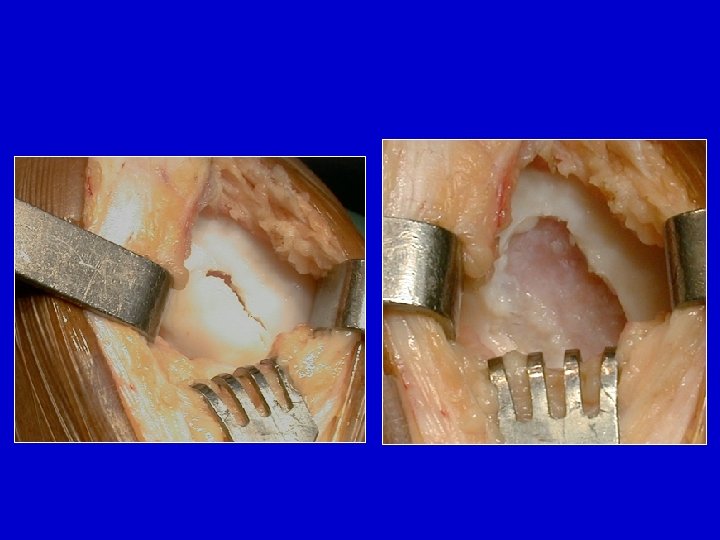

Osteocondrite aperta , il frammento è ancora in posizione

La nicchia , spesso, é coperta da tessuto fibroso

Aspetto dei corpi estranei osteocartilaginei